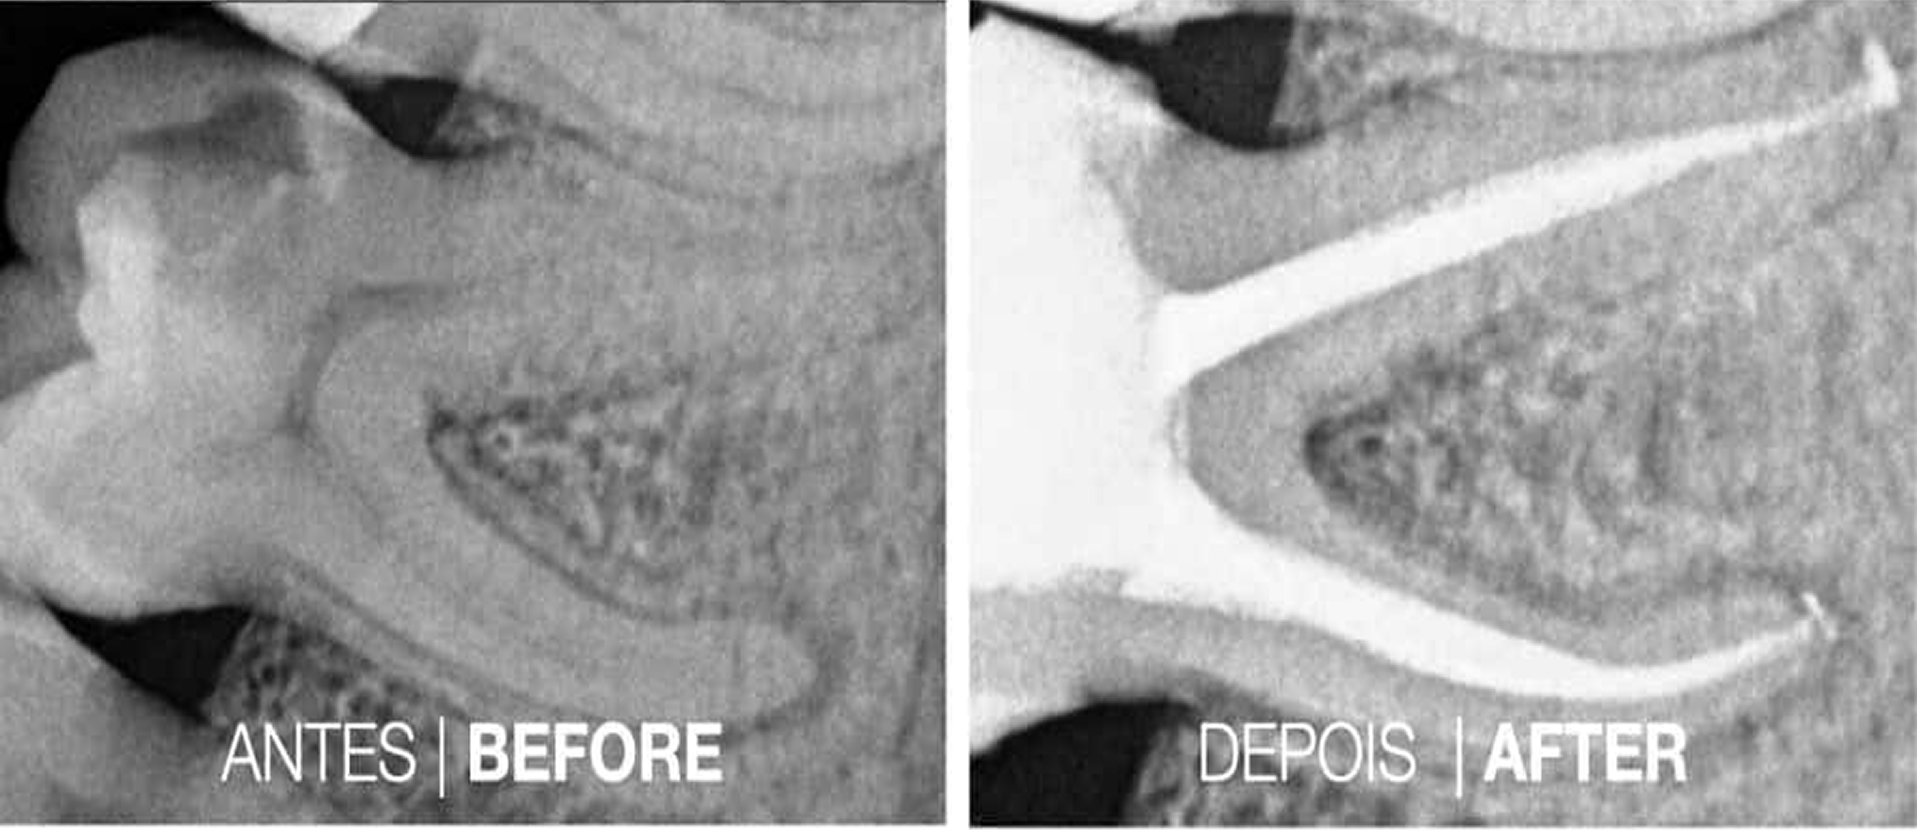

Casos Clínicos

Casos Cínicos concretos que revelam a eficácia do tratamento.